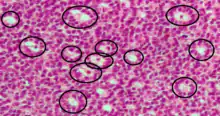

Call–Exner bodies marked with black circles in an intermediate-high magnification micrograph of a granulosa cell tumour, a type of sex cord stromal tumour. H&E stain.

Call–Exner bodies, giving a follicle-like appearance, are small eosinophilic fluid-filled punched out spaces between granulosa cells.[1] The granulosa cells are usually arranged haphazardly around the space.

They are pathognomonic for granulosa cell tumors.

They are composed of membrane-packaged secretion of granulosa cells and have relations to the formation of liquor folliculi which are seen among closely arranged granulosa cells.